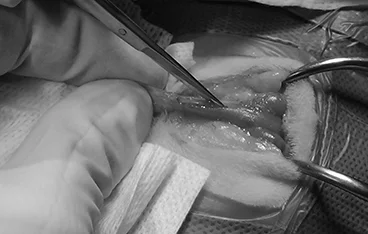

외이도 종괴, 외이염&중이염&내이염

TECA+LBO / VBO

• TECA+LBO 수술 전

TECA+LBO 수술 후

• VBO